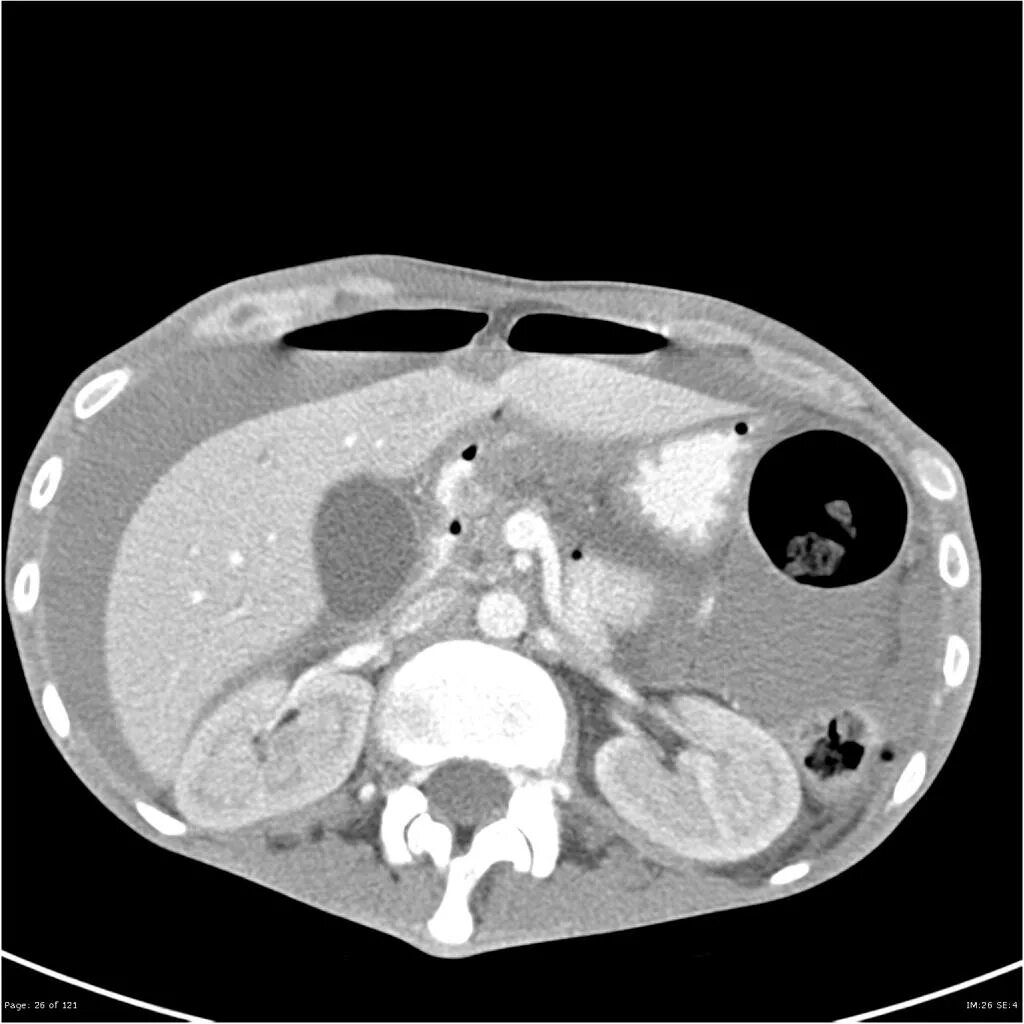

Язва желудка кт